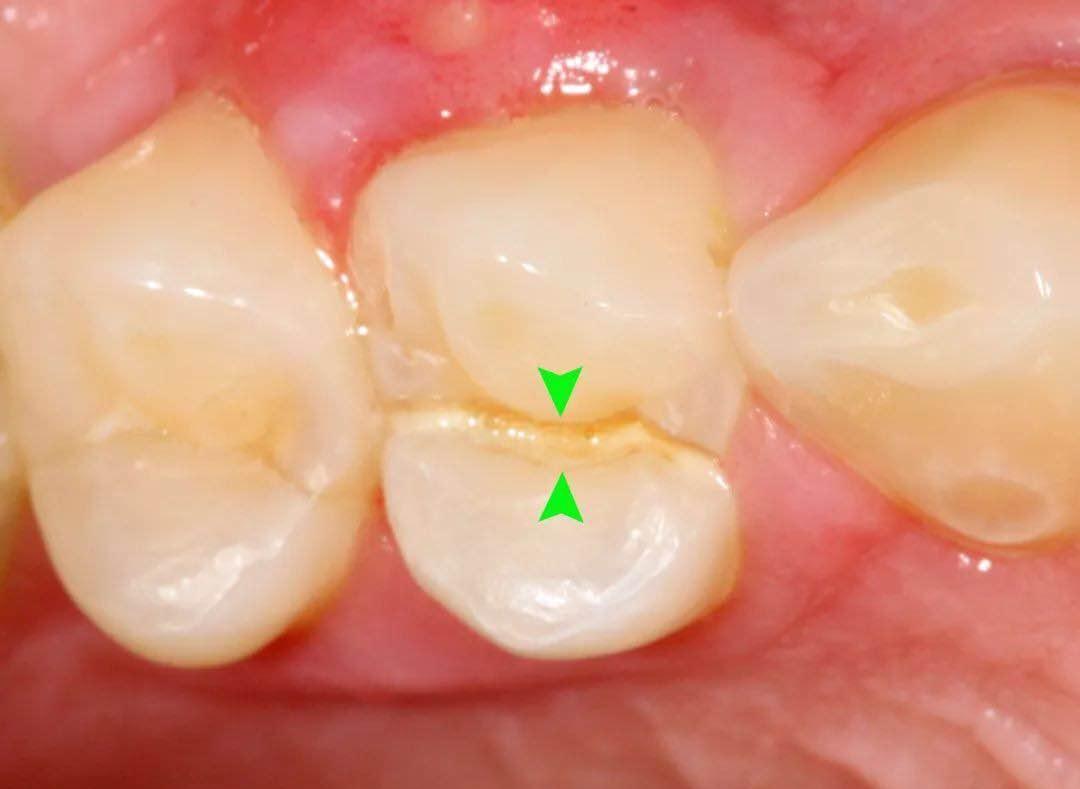

2、裂纹深达牙本质但未累及牙髓组织

当牙齿受外力较大,裂纹深达牙本质层但未累及牙髓组织,因牙本质暴露,外界的刺激就可经裂纹进入激惹牙神经,患者可出现冷热刺激痛,但无自发痛。此种情况磨除裂纹部分行树脂充填也能非常有效消除疼痛。